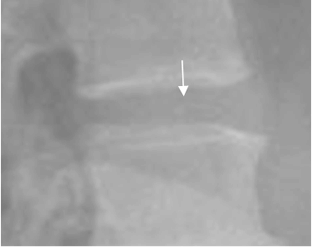

En la Rx se encuentra disminución del espacio intervertebral, fenómeno del vacío central o cerca del hueso subcondral y calcificación. (3, 6). (Fig 32 y 33).

El fenómeno del vacío corresponde a nitrógeno acumulado por la presión negativa, que se produce al disminuir el espacio intervertebral. Se aprecia como imagen con densidad de aire en la RX y el TAC o ausencia de señal en la RM. (4). (Fig 34 y 35).

Fig 34. Fenómeno del vacío.

A: Rx lateral, B: TAC reconstrucción sagital y C: RM sagital en T1. Presencia de aire dentro de los discos, por proceso degenerativo.